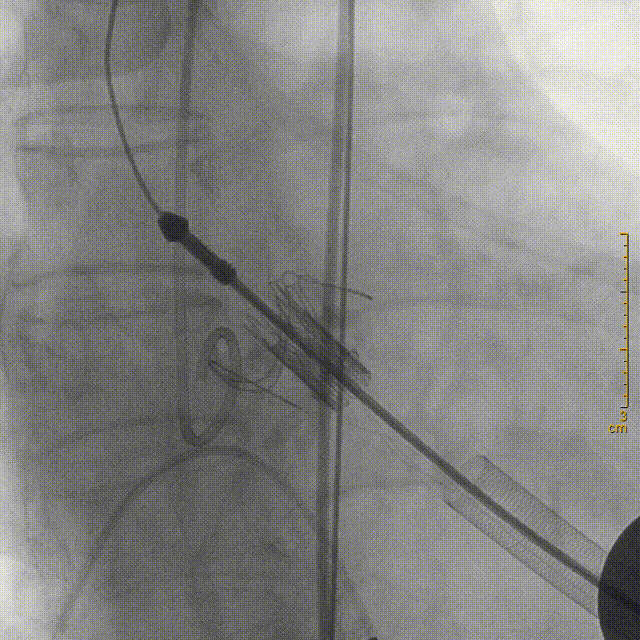

主动脉根部造影,确定瓣环位置

20mm球囊预扩张

将装置好J-Valve23mm主动脉瓣的输送鞘送至主动脉瓣瓣环平面,释放定位装置并造影定位

稳定释放瓣膜

严重钙化使瓣膜形态未完全展开

球囊扩张后,瓣膜形态完美,超声复查无瓣周漏,冠脉开口无堵塞